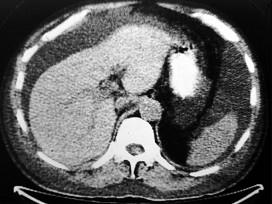

问题 下列图像最佳诊断是什么 ( )

选项 A.肝脓肿 B.肝炎肝硬化 C.肝包虫病 D.原发性肝癌 E.肝血管瘤

答案 B